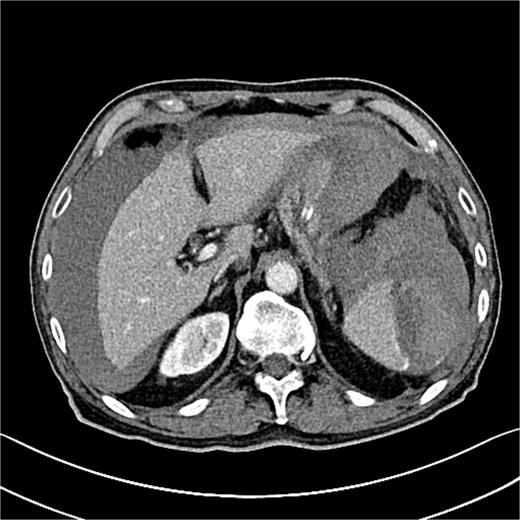

Seven hours post-procedure, the patient presented to the emergency department with abdominal pain, syncope, diaphoresis, and bloating. His blood pressure was 80/50 mmHg, and his heart rate was 120 beats per minute. Abdominal examination revealed tenderness in the left hypochondrium, and his hemoglobin level was 6.2 g/dl with a hematocrit of 38%. A contrast-enhanced abdominal computed tomography (CT) scan showed a ruptured spleen with a 7-cm parenchymal hematoma, a significant blood halo surrounding the liver, and a large blood accumulation of 15 × 12 cm in the pelvis (Figs 1 and 2).

Grade III splenic injury with intraparenchymal hematoma larger than 5 cm [5].